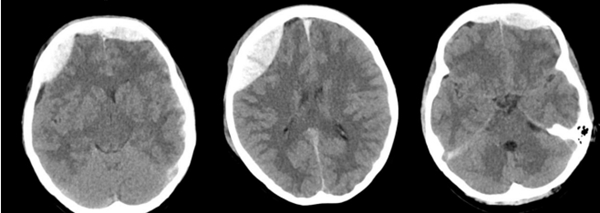

近日,中山大学附属第一医院(简称中山一院)广西医院神经外科团队成功救治一名因外伤导致迟发性硬膜外血肿的患者,经开颅硬膜外血肿清除术后,患者最终康复出院,并为科室送来一面写有“医术精湛挽危厄,仁心厚德臻至善”字样的锦旗,表达对科室全体医护人员感谢。患者黄女士(化名)是一名警员。因意外受伤被送到我院急诊科救治。我院立即启动绿色通道,为患者进行全面检查,头颅CT提示,额骨、右顶骨有20...